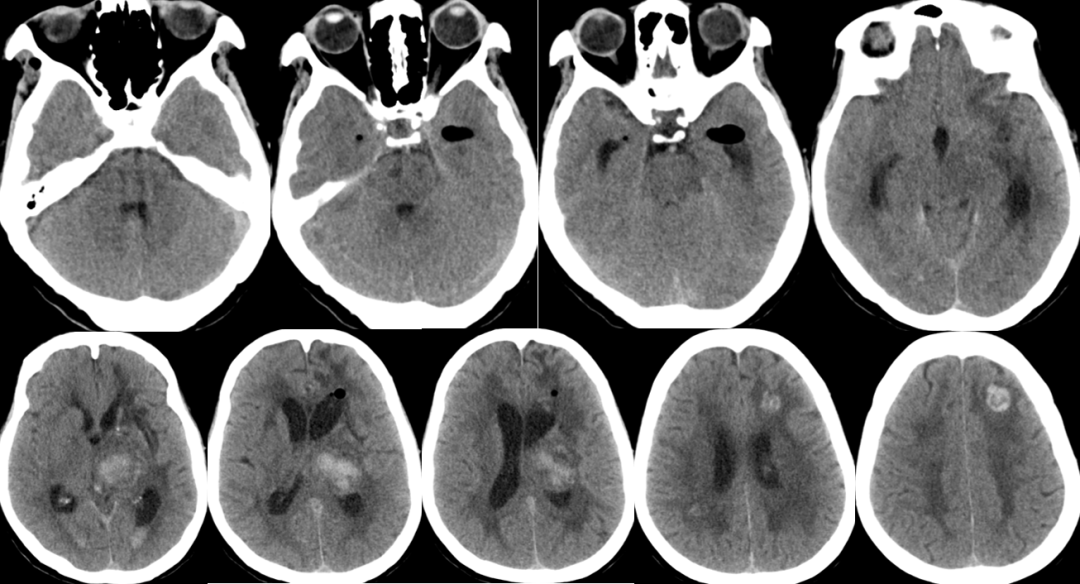

脑干梗塞?

2014-11-27 MRI

2014-11-27 CT

2014-12-2 CT